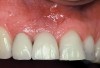

The importance of establishing periodontal health prior to both implant placement and the treatment of peri-implantitis has been discussed in numerous studies.22,28,29 In addition, properly contoured restorations on implants are essential in allowing a patient to maintain good plaque control following any surgical intervention. This may entail removal of an ill-fitting or poorly contoured crown and creating a well-fitting provisional prior to surgery (Figure 2 and Figure 3). In a study of 23 subjects who presented for treatment of peri-implantitis, it was reported that 74% of their implants diagnosed with peri-implantitis were associated with no accessibility/capability for proper oral hygiene. The authors emphasized the importance of proper prosthetic constructions that allow accessibility for oral hygiene around implants.30 Patients should also be taught proper homecare methods prior to surgery, to minimize plaque accumulation during and following treatment to ensure optimum healing of the peri-implant tissues.

Figure 2  A poorly contoured implant restoration preventing effective patient homecare.

Figure 2